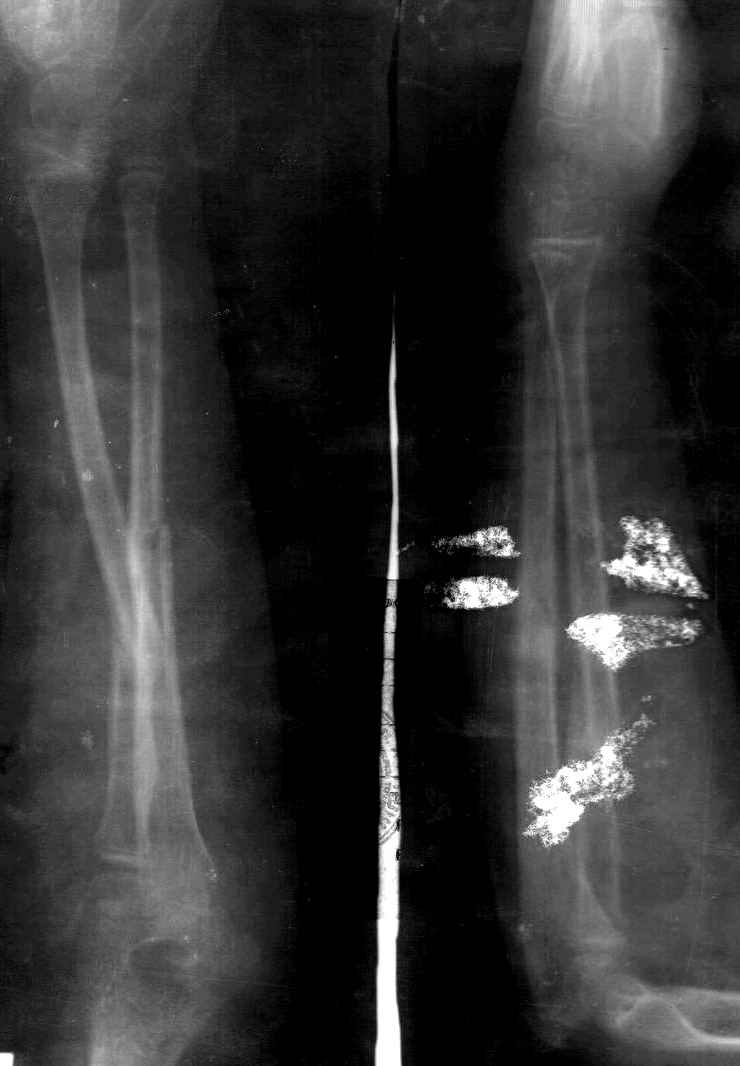

Сделал симметричные снимки с максимальной супинацией и пронацией при согнутом предплечье в 90 град. Объем ротационных движений 90-100 град.

СМ> Сделал симметричные снимки с максимальной супинацией и пронацией при

СМ> согнутом предплечье в 90 град. Объем ротационных движений 90-100 град.

Снимок один сделан с супинацией, второй - оба предплечья в одинаково нейтральном положении. то есть по этим снимкам объем ротационных движений не оценить. Снимко в двух проекциях лучше и делать в среднем положении между пронацией и супинацией, то есть обе проекции в однм и том же положении, когда линия, проходящая через шиловидные отростки, идет в плоскости головки. Прошу прощения за усложнение простых вещей.